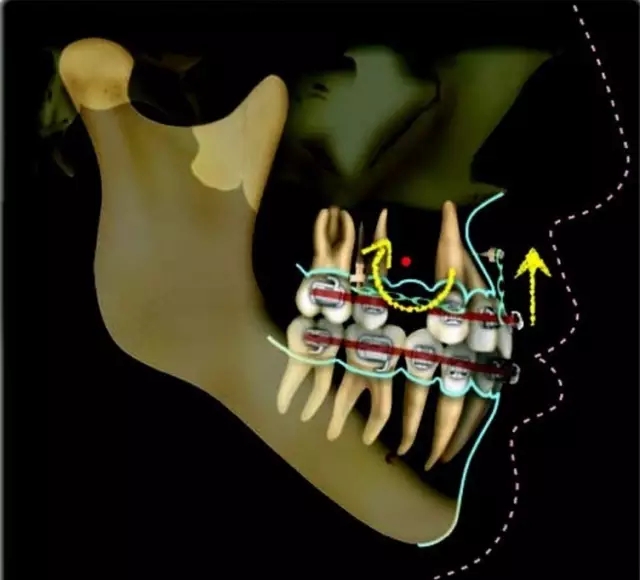

Damon 病例分享:安氏 II 類(lèi)二分類(lèi)露齦笑的矯治(董一磊)

患者信息

治療前后對(duì)比